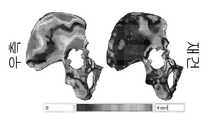

도 9는 비구 결함에 대한 기존의 AAOS 분류의 도시 예이다.

도 10은 기존의 Paprosky 비구 결함 분류의 도시 예이다.

도 14의 좌측은 심각한 골반 불연속성을 갖는 환자의 3차원적 모델 표상이다. 우측에는 좌측에 나타낸 상기 환자의 골반의 3차원적 모델에 대한 일 예가 도시된다.

The left side of FIG. 14 is a three-dimensional model representation of a patient with severe pelvic discontinuity. On the right, an example of a three-dimensional model of the patient's pelvis shown on the left is shown.